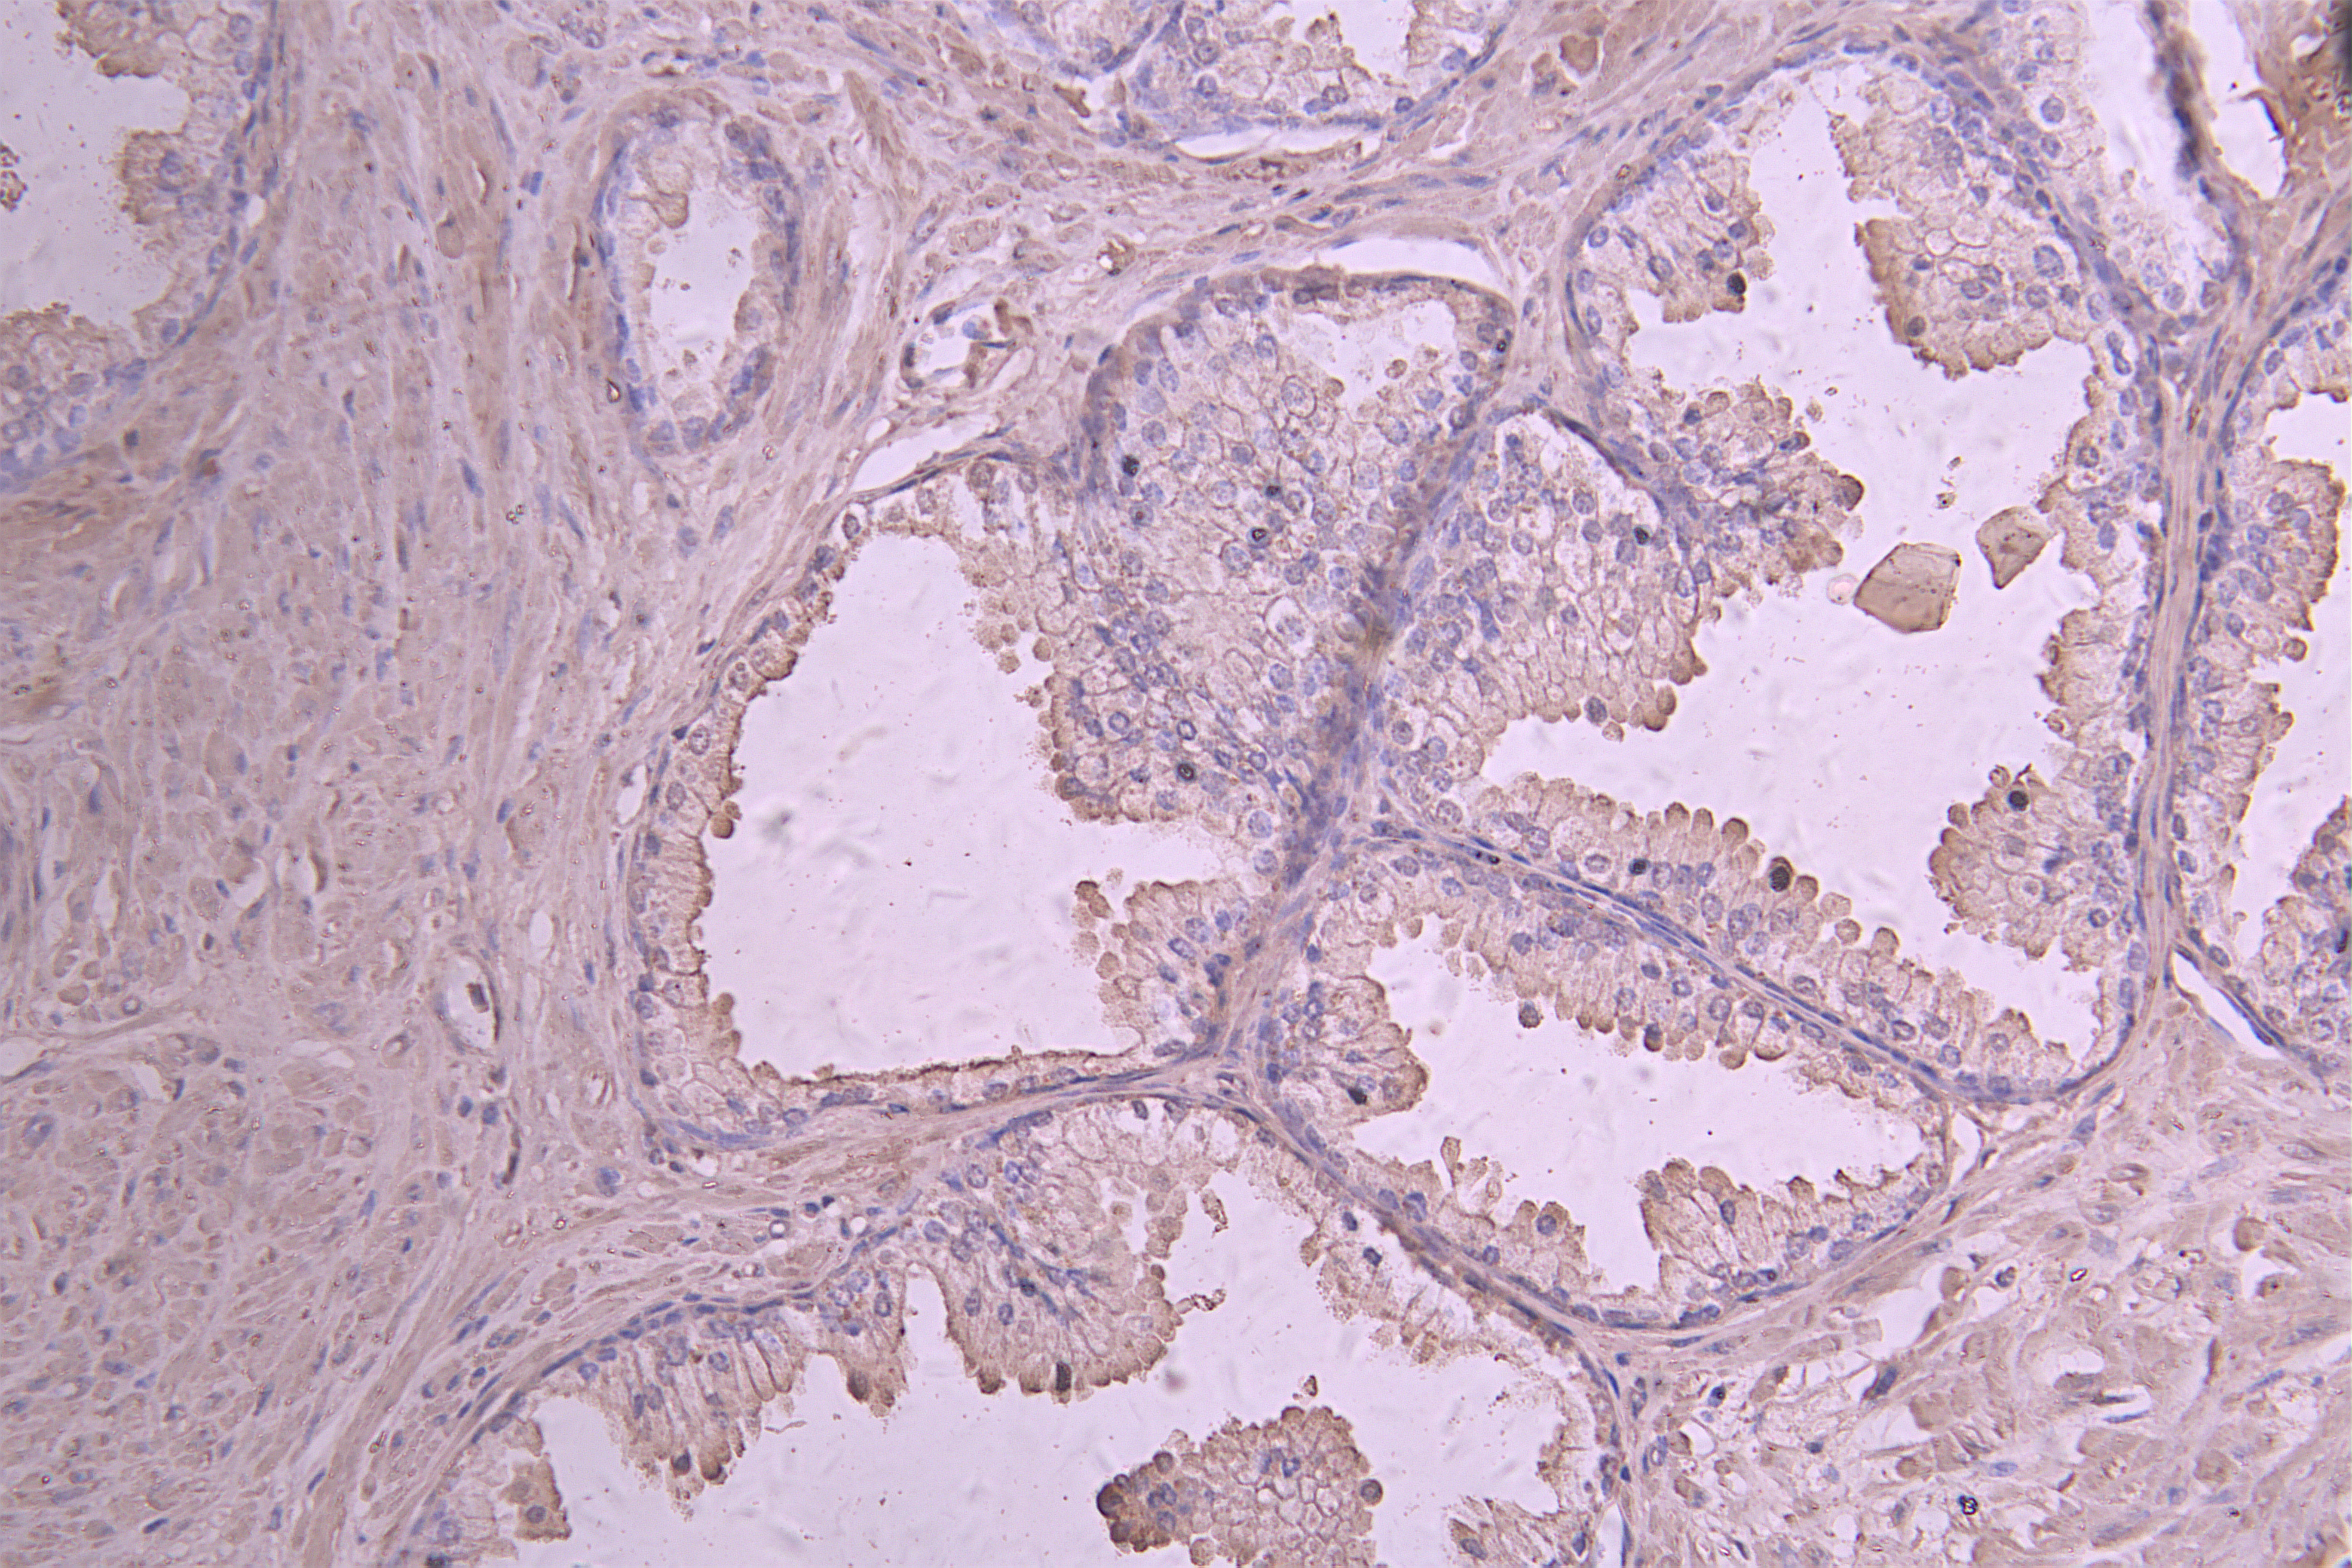

IHC image of CSB-RA011586MA1HU diluted at 1:50 and staining in paraffin-embedded human prostate cancer performed on a Leica BondTM system. After dewaxing and hydration, antigen retrieval was mediated by high pressure in a citrate buffer (pH 6.0). Section was blocked with 10% normal goat serum 30min at RT. Then primary antibody (1% BSA) was incubated at 4°C overnight. The primary is detected by a Goat anti-human polymer IgG labeled by HRP and visualized using 0.05% DAB.